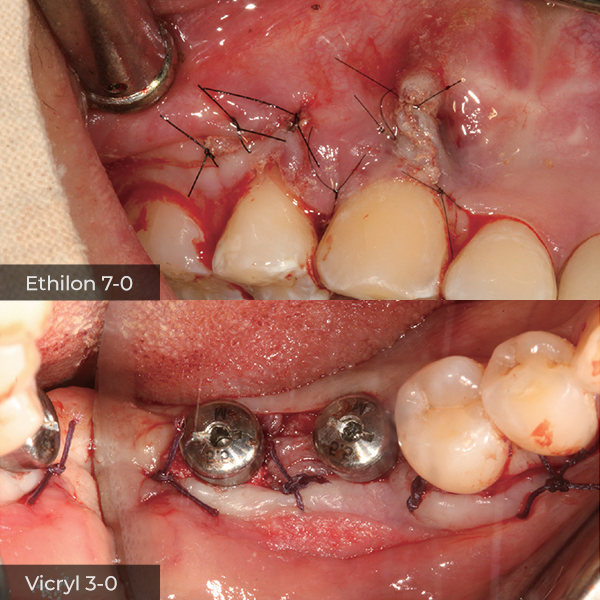

Director’s Clinical Cases

Director’s Clinical Cases